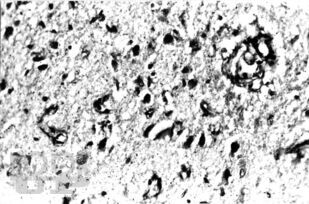

В руководстве обобщен практический опыт и анализ современной литературы по диагностике и лечению 30 редких или атипично протекающих неврологических синдромов и болезней. Обсуждаются аспекты этиопатогенеза, клинической картины, дифференциальной диагностики, наиболее типичные тактические и терапевтические ошибки.